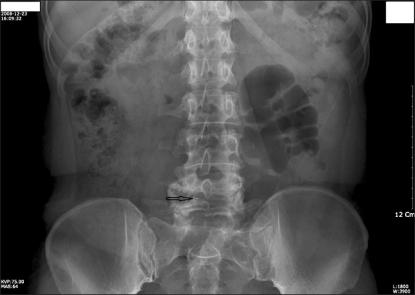

Lumbar epidural anesthesia is useful in a variety of chronic benign pain syndromes, including lumbar radiculopathy, low back pain syndrome, spinal stenosis, and vertebral compression fractures. Given the increased number of epidural nerve blocks being performed, some have reported unexplained complications of a transient or permanent nature and with varying degrees of severity. However, no case has been reported of a broken epidural needle tip retained in the lumbar facet joint area. This represents the first reported case presentation of foraminal stenosis developing in a patient after a retained epidural needle tip.

腰椎硬膜外麻醉在多种慢性良性疼痛综合征中都很有用,包括腰椎神经根病、腰痛综合征、椎管狭窄和椎体压缩性骨折。由于硬膜外神经阻滞的数量增加,一些人报告了一些原因不明的、暂时或永久性的、严重程度不同的并发症。然而,尚未有报告称硬膜外针尖端断裂并残留在腰椎小关节区域的病例。这代表了首例在残留硬膜外针尖端后发生椎间孔狭窄的患者病例报告。